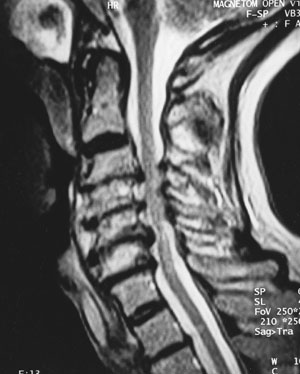

Çoğu hastada, hastanın şikayeti ve muayene oldukça işe yarar. Düz röntgen filmleri, boyundaki fıtığa ait düzleşme, eklem aralığında daralma, boynun açılanması ve kireçlenmelerini gösterir. MR ve tomografi boyun fıtığının ve kireçlenmelerinin değerlendirilmesinde ileri tetkik metodlarıdır, ve çoğu hastada gerekli değildir.